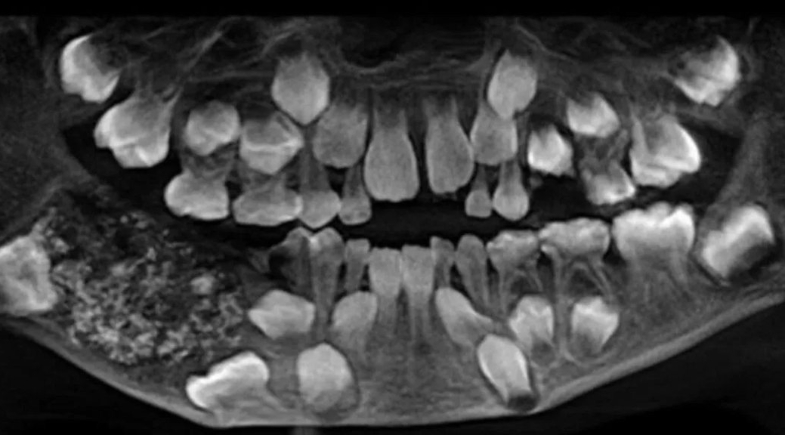

Caso raro de odontoma composto surpreendeu médicos em Chennai, na Índia | Foto: Saveetha Dental College and Hospitals/Divulgação

O que parecia um simples inchaço no maxilar de uma criança acabou revelando um dos episódios mais impressionantes já registrados pela odontologia mundial. Em Chennai, na Índia, um menino de sete anos passou por uma cirurgia na qual foram extraídos 526 dentes em miniatura de sua mandíbula. O caso que surpreendeu especialistas de todo o mundo, foi registrado em 2019.

Depois da investigação, os médicos constataram tratar-se de um odontoma composto, um tumor benigno formado por tecidos dentários. Durante a cirurgia, foi removida uma massa de cerca de 200 gramas que continha uma espécie de bolsa fechada. Dentro dela, os cirurgiões localizaram centenas de estruturas semelhantes a dentes.

“Foram necessárias cinco horas de busca meticulosa para remover todos os dentes minúsculos do espécime, que lembrava pérolas em uma ostra”, destacou o hospital em comunicado. As peças retiradas variavam de 1 a 15 milímetros, mas todas possuíam características completas de dentes, incluindo coroa com esmalte e raiz.

A equipe descreveu o achado como “uma verdadeira caixa de Pandora de dentes em miniatura”. Segundo a instituição, este foi o primeiro caso no mundo em que tantos dentes foram identificados em um único paciente.